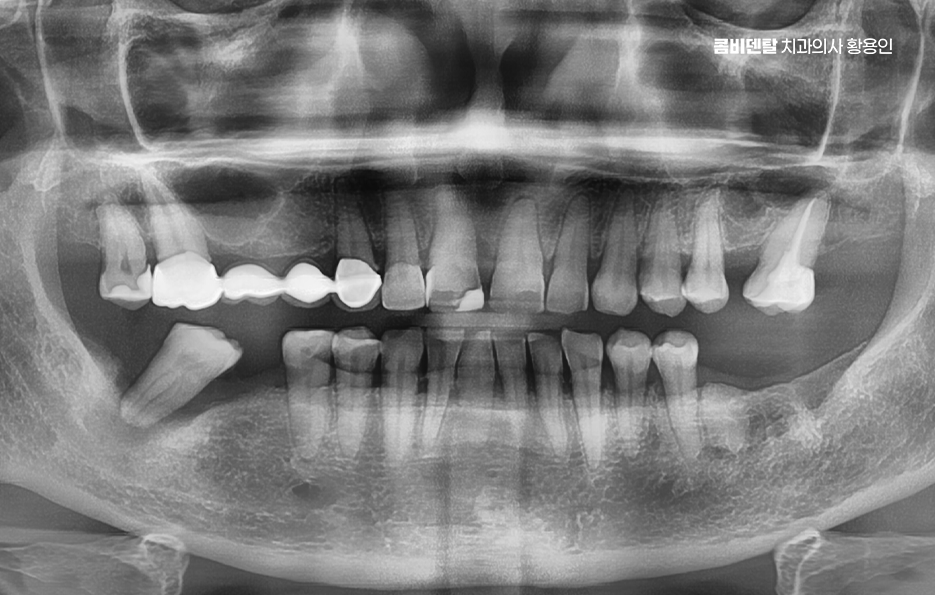

출처 아카이브 열기이를 하나 잃고 나니까 생각보다 공백이 크더라고요, 단지 어금니 하나 빠졌을 뿐인데, 씹는 균형이 무너지는 건 물론이고, 마음까지 허전해지는 기분이 들었어요, 처음에는 ‘한쪽으로만 씹어도 되겠지, 불편하면 다른 쪽을 쓰면 되니까’라는 생각으로 버텼는데, 갈수록 턱이 아프기 시작하고, 음식물을 씹는 것도 예전처럼 자연스럽지가 않았어요, 그러다 문득 든 생각이 ‘이걸 그냥 둘 수는 없겠구나’였어요, 임플란트라는 이름은 많이 들어봤지만 막상 내가 하게 될 줄은 몰랐고 막상 알아보려고 하는 막막했어요 임플란트가 좋다고들 하는 이유를 들으면, 가장 먼저 나오는 말이 ‘자연치아처럼 사용할 수 있다’는 거였어요, 말은 참 간단한데 그 의미를 제대로 이해한 건 치아를 잃고난 다음이었어요 잇몸만 남은 채로 한쪽으로만 음식을 씹을 때 느껴지는 불편함은 단지 물리적인 게 아니라 심리적인 위축도 함께 따라왔어요, 어떤 음식은 피하게 되고, 무심결에 씹다 통증이 올라오면 입맛도 뚝 떨어지고, 일상 속 식사가 스트레스로 바뀌기도 했어요

이처럼 치아 상실 후에 그대로 방치하게 되면 생각보다 다양한 문제점들이 연쇄적으로 나타나게 되는데 요즘은 임플란트가 대중적으로 보급되었음에도 내가 막상 치료 받아야 하는 상황이 되면 막막함 부터 느끼시는 분들도 많이 있었어요

임플란트는 사실 잃어버린 자연치아를 기능적으로도, 심미적으로도 유사하게 복원할 수 있는 정교한 치료 방법으로 자연치아처럼 씹고 말하고 웃고 생활할 수 있게 해주는 대체 치료임에도 잘 몰라서 망설이시는 분들도 많다는 점에서 이 임플란트라는 게 어떤 원리로 작동하는 건지, 임플란트의 장점은 무엇인지 정확하게 이해하는 것이 치료 계획을 세우는데 도움이 될 거예요